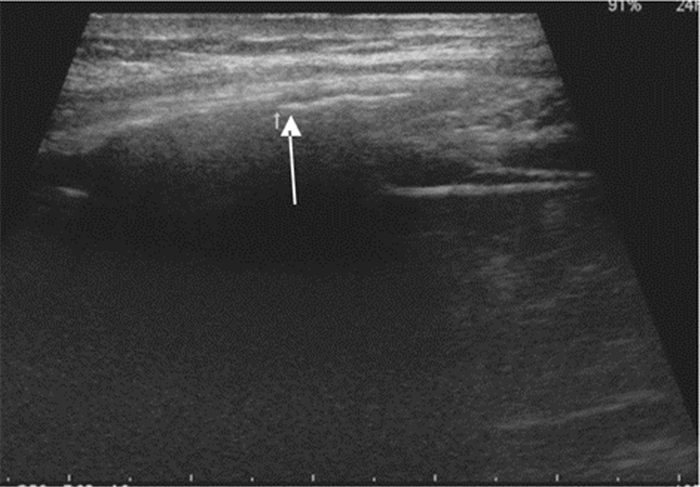

2.2.5 肝样变、碎片征大片肺实变时,实变肺组织呈现类似肝实质样软组织回声(图 12)。小片肺实变表现为不规则的碎片状强回声,即“碎片征”(图 13)。研究显示超声对厚度大于20 mm的肺实变检测阳性率较高,其总体敏感度和特异度分别为90%和98%。

| 图 12 大片肺实变:箭头示肺组织呈软组织回声改变 |

| 图 13 小片肺实变:箭头示肺组织呈碎片样改变 |

其可能的机制为外周肺组织缺血,可见于肺栓塞或间质性肺炎患者。